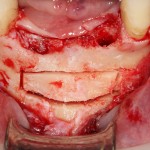

Остеопластические операции: факторы успеха. Часть II.